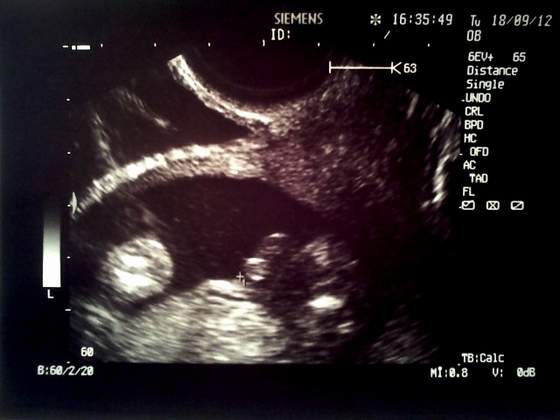

Dziewczyny, śliczne zdjęcia!!!!!

Piękne i niepowtarzalne zdjęcia:-)

smoniczkowa stópka jest super

Smoniczka gratuluję udanej wizytki i ...stopa jak ta lala